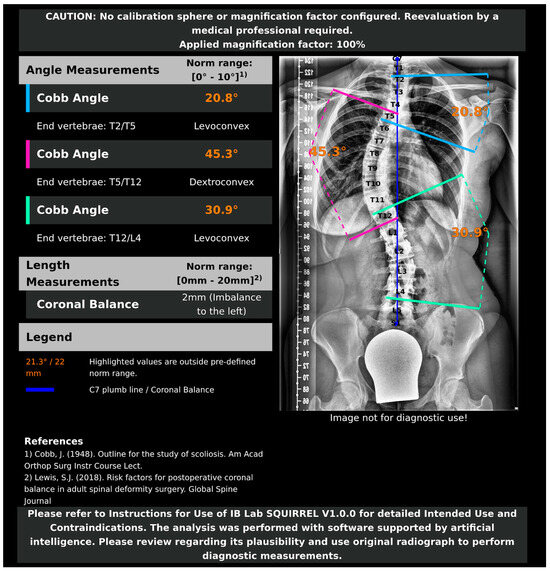

2.3. AI Model and Algorithms